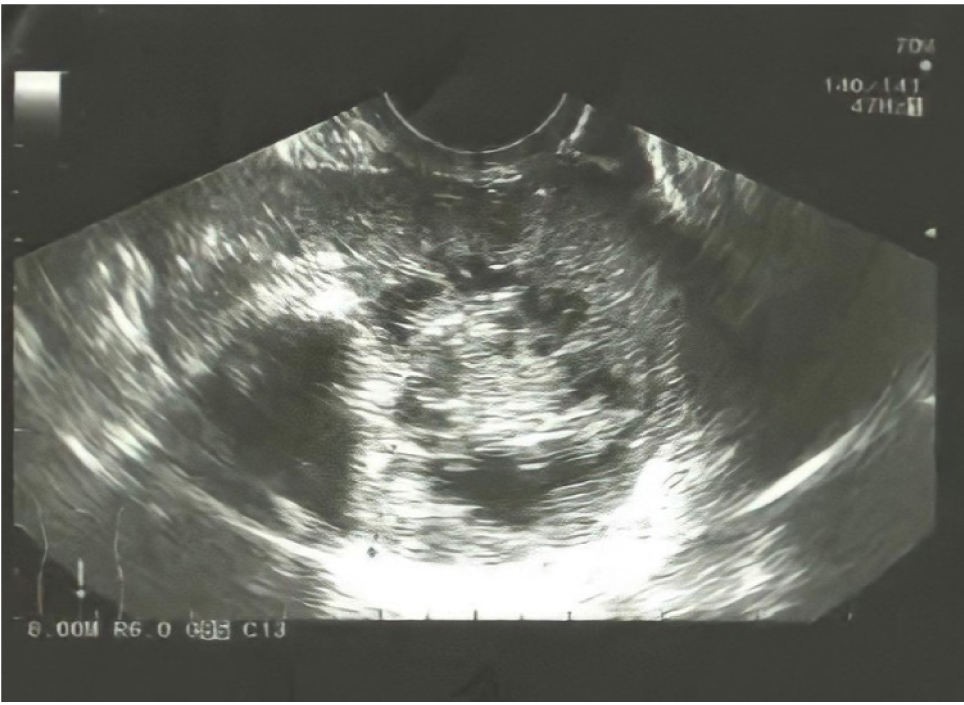

При МРТ: картина кистозно-солидного внеорганного гиповаскулярного объемного новообразования в позадиматочном пространстве, диаметром до 5 см. В марте 2021 года было проведено оперативное вмешательство: удаление объемного жидкостного образования в плотной капсуле. Гистологическое исследование: гранулема полости малого таза. На контрольном УЗИ в августе 2021 года (рис. 2) вновь выявлены признаки объемного образования малого таза, кровоток достоверно не визуализирован. Пациентка направлена на дальнейшее лечение в хирургическую клинику.

Рис. 2. Объемное образование позадиматочного пространства, принятое за рецидив гранулемы, кровоток достоверно не визуализирован